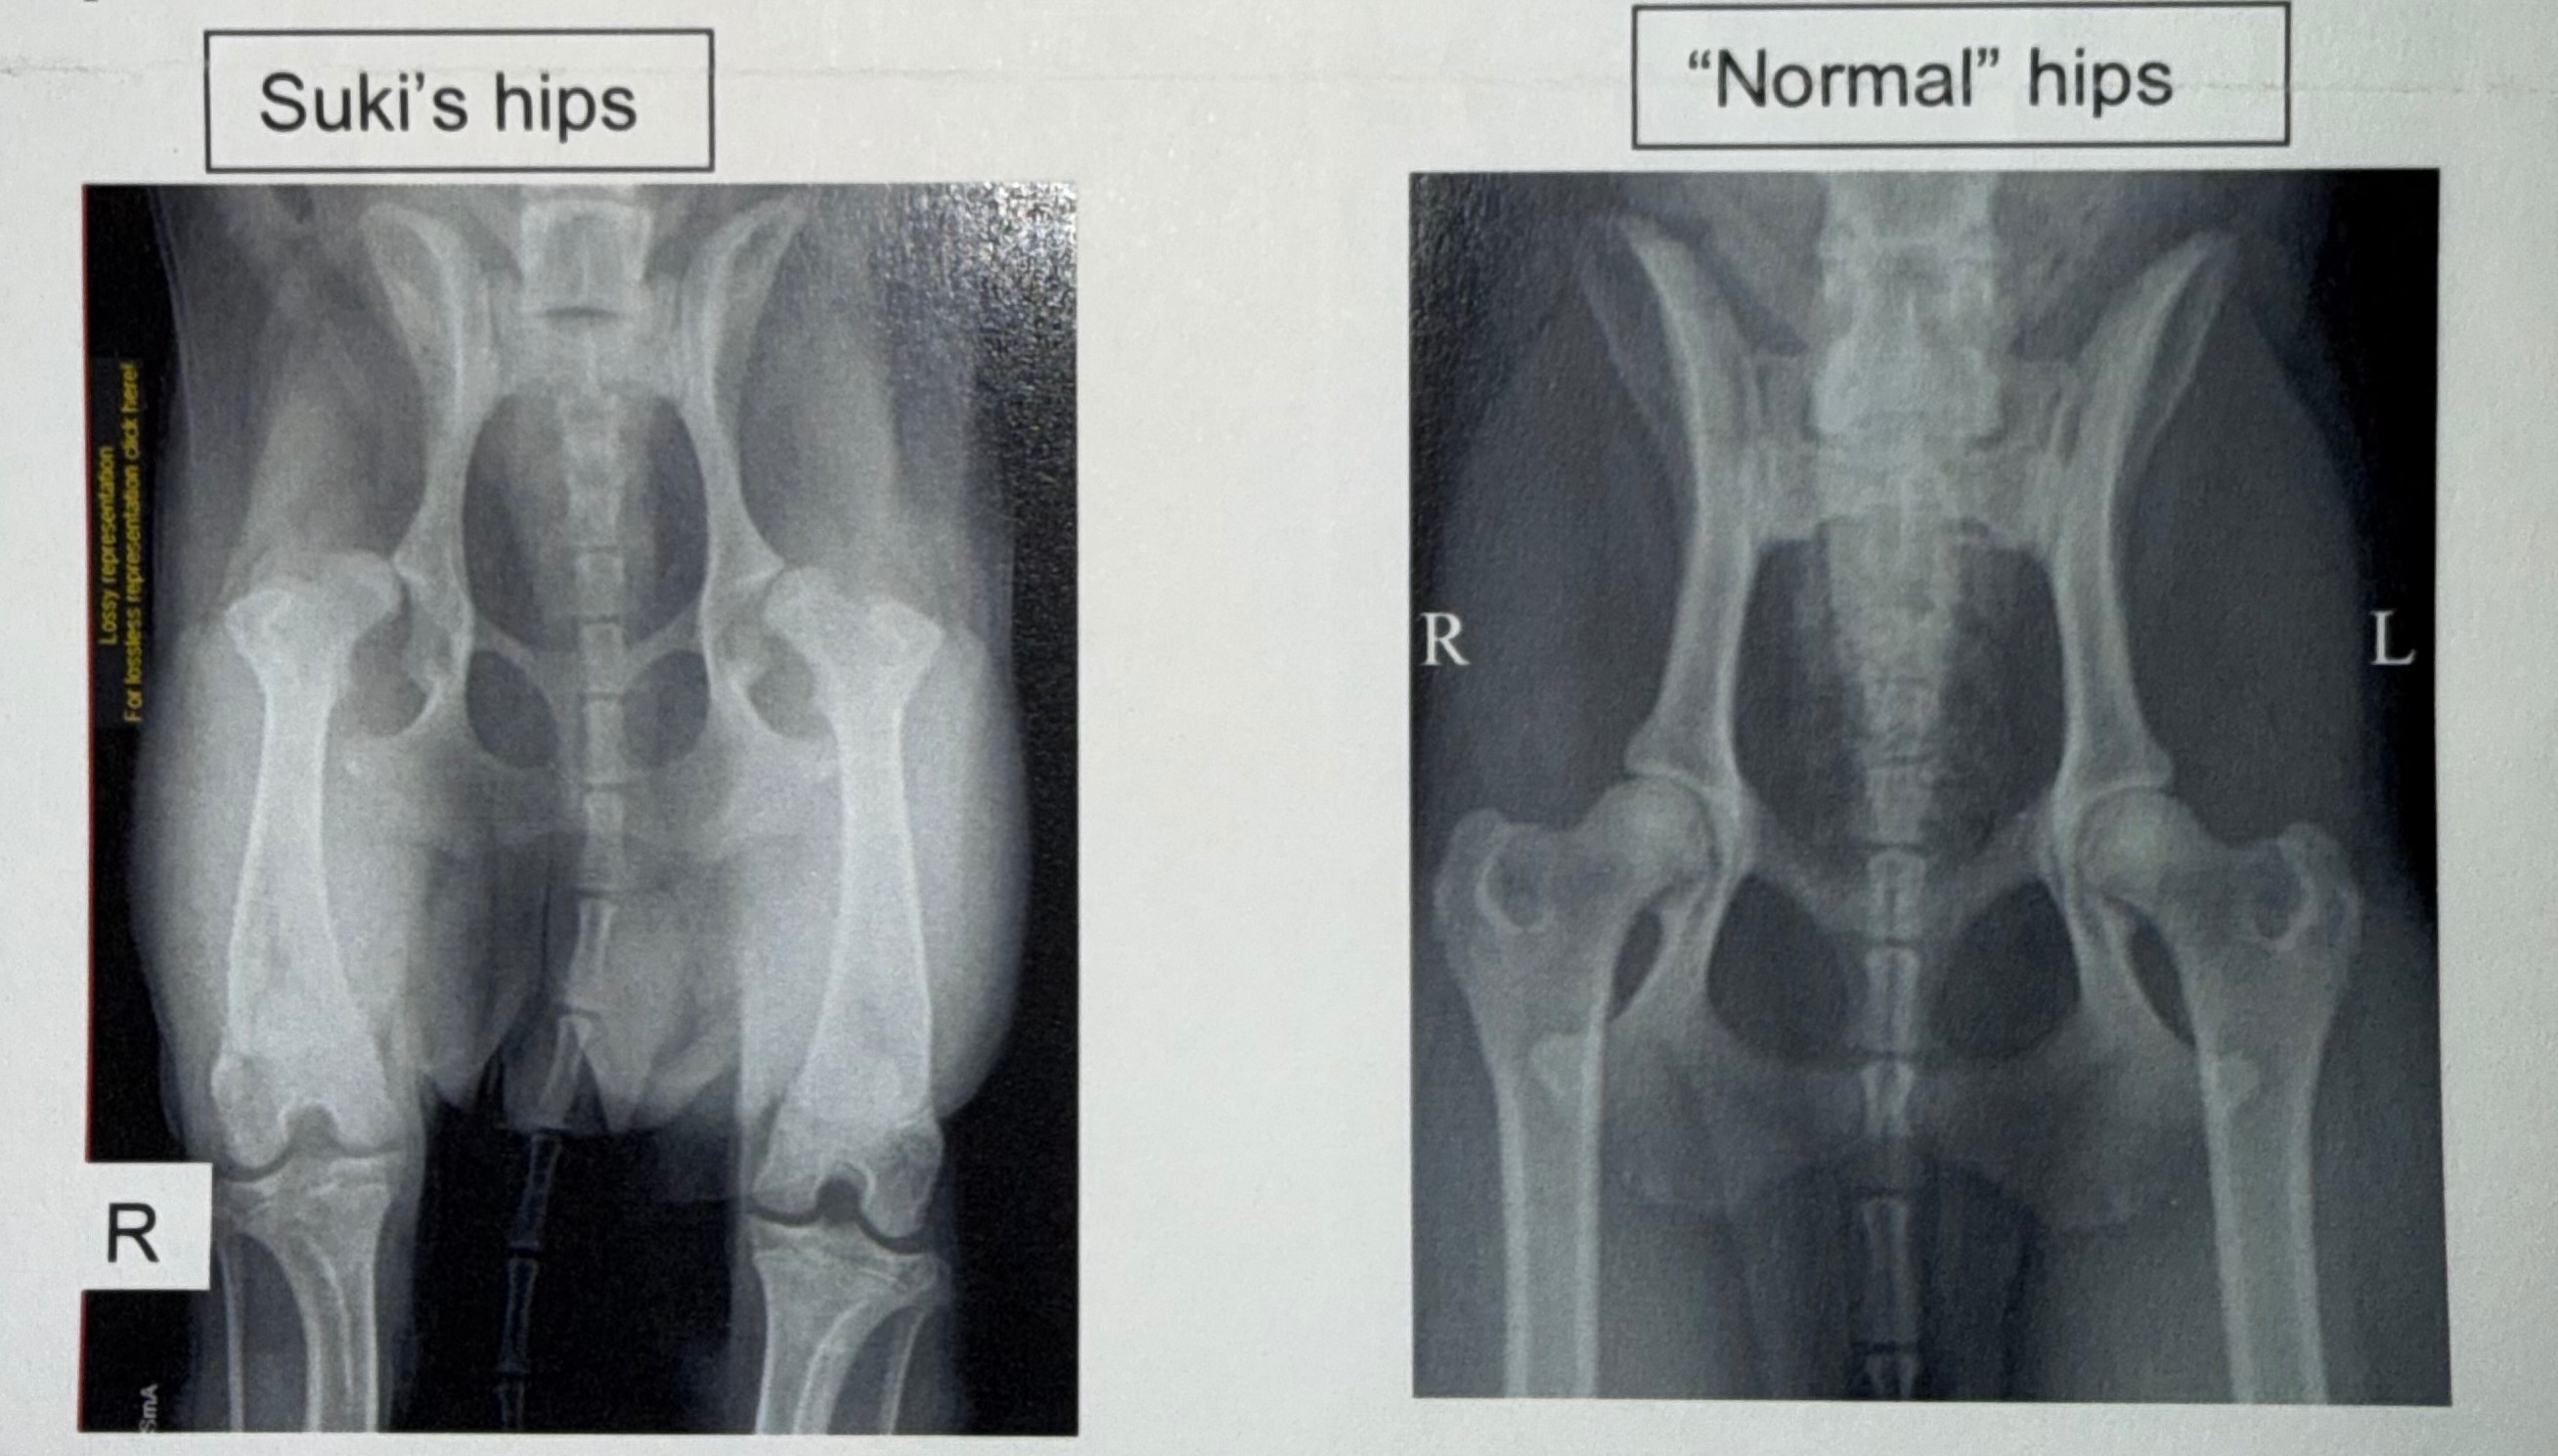

My beautiful dog Suki has severe hip dysplasia and when she was just 10 months old, she had her first total hip replacement back in 2021.

Unfortunately, Suki has now reached a point where her other hip is causing her pain and stopping her from enjoying the things she loves most.

FYI - photos of the X-RAY are from before and after her 2021 surgery. I’m awaiting pictures of the CT done today and will add these once they arrive!!